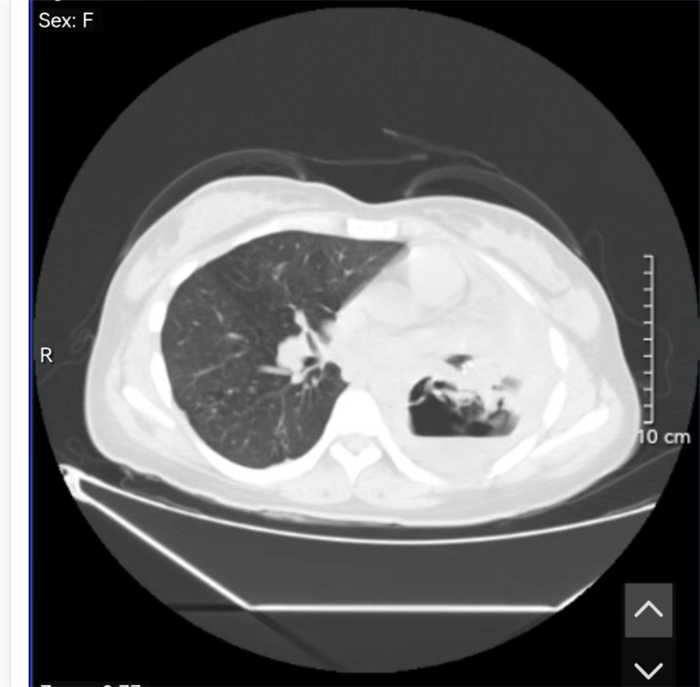

医生在做CT影像检查时发现,她的左肺里面的组织已经被结核菌“吃”掉了,形成了巨大的空洞,空洞里有脓液。

▲ 右边空白部分就是被细菌“吃”掉的

医生告诉记者,结核分枝杆菌不仅伤肺,还会“吃掉”肺脏。正常情况下,肺部充满气体,做CT时应该是黑色透亮的。但罹患肺结核后的患者,肺部CT影像会出现空洞及肺组织纤维化收缩,像被“吃掉”了一样。